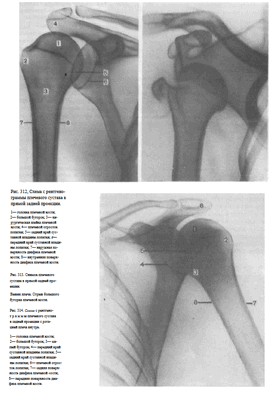

На снимках плечевого сустава хорошо видны головка плечевой кости, суставная впадина лопатки, плечевой отросток лопатки.

На рентгенограмме, произведенной в условиях супинации кисти, хорошо виден большой бугорок плечевой кости, который здесь является краеобразующим (рис.312, 313). На снимках, произведенных в условиях пронации кисти, большой бугорок виден хуже, но по медиальному контуру над хирургической шейкой становится виден малый бугорок (рис.314). Медиальный и латеральный контуры тела плечевой кости при этих двух вариантах укладки на снимках образованы разными ее поверхностями. На снимке при супинации кисти медиальный контур образован внутренней, а латеральный — наружной поверхностью тела плечевой кости; на снимке при пронации кисти медиальный контур отображает переднюю, а латеральный — заднюю поверхность тела плечевой кости.

Краеобразующими являются малый бугорок плечевой кости, передняя поверхность диафиза плеча по верхнему контуру и задняя поверхность диафиза плеча по нижнему контуру (рис.318, 319).